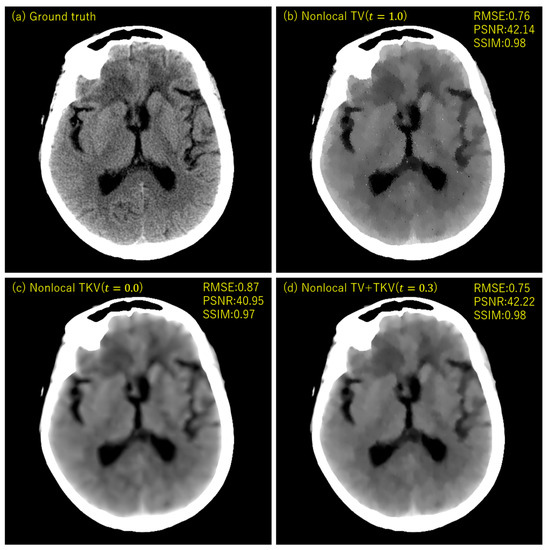

3. Experimental Results

4. Discussion